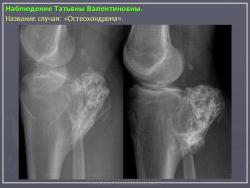

Наблюдения коллег.